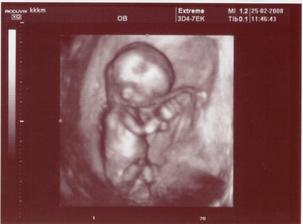

Naše druhé zlatíčko

Tak 9. DPO (19. 12.) se na testu objevila slaboučká čárka, 11. DPO těhu potvrzeno z krve, termín porodu zatím máme 1. 9. 2008....